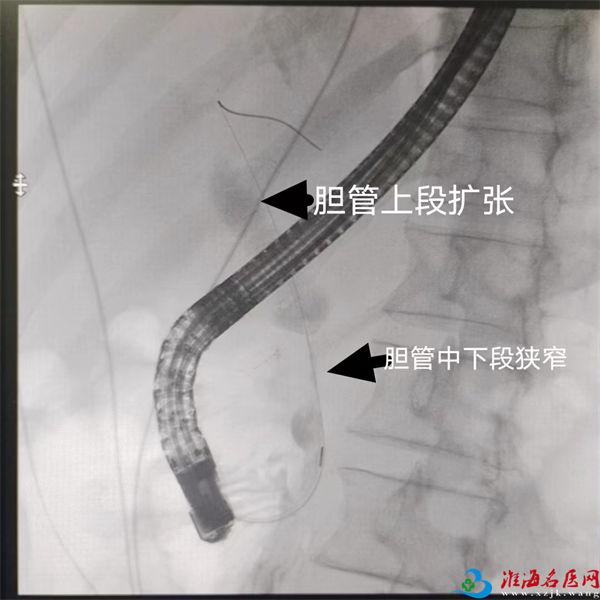

X造影见胆总管中下段狭窄

入院次日,在麻醉团队、内镜中心护士长曹琳琳及主管护师戴文帝的紧密协作下,陈新孚和副主任医师陈卓团队成功为李先生实施了ERC+内镜下胆管支架置入术+胆管冲洗术。术中,胆管支架的植入有效缓解了梗阻症状,大量脓液被引流而出,李先生的状况迅速好转。